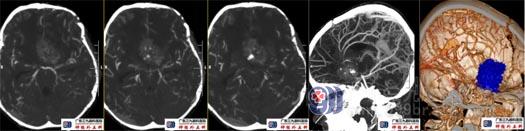

术前头颅MRI示左侧额颞部呈术后改变,鞍内术区示团块状各序列高信号为主的高低混杂异常信号影,大致同前,增强扫描边缘强化同前。鞍上-左侧额叶-侧脑室前角示团块状占位性病变范围较前增大,呈偏等T1、不均匀短T2异常信号影,间杂少许稍短T1信号,Flair序列呈等低信号,增强后明显强化,周围示片状长T1、长T2,Flair序列高信号影范围较前明显增大,累及双侧额叶、胼胝体及基底节区。幕上脑室扩张。中线结构居中。鞍上-左侧额叶-侧脑室前角颅咽管瘤术后较前明显增大,周围水肿明显进展。